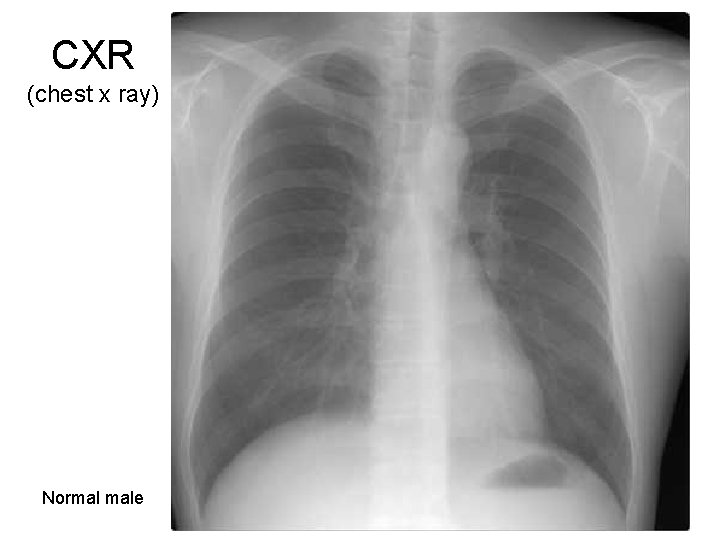

CXR (chest x ray) Normal male 7